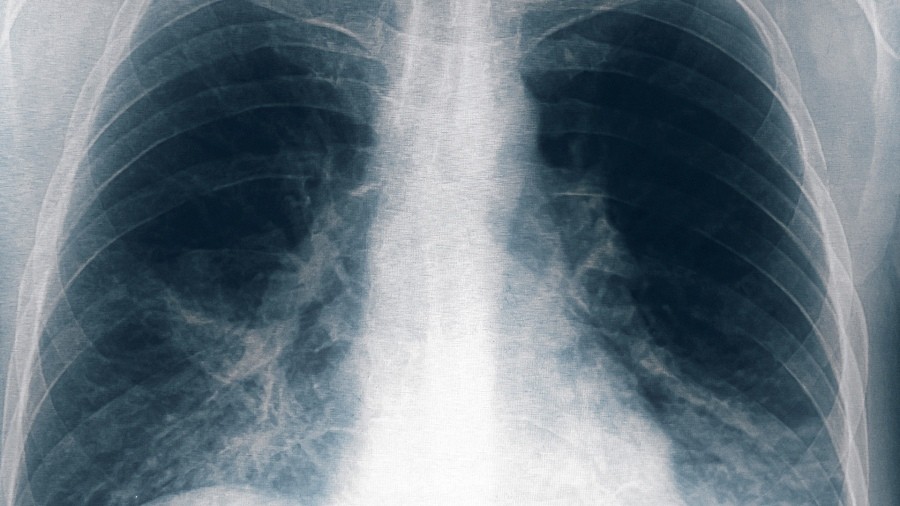

Conocida también como Enfermedad del Legionario, es un tipo de neumonía grave, una infección en los pulmones.

Otras ocho personas resultaron afectadas por el brote de neumonía bilateral causado por la bacteria legionella, una de ellas en estado grave, tras un cambio en el criterio de selección de los pacientes, con lo que suman 13 casos en total y seis fallecidos, informó el ministro de Salud de Tucumán, Luis Medina Ruiz.